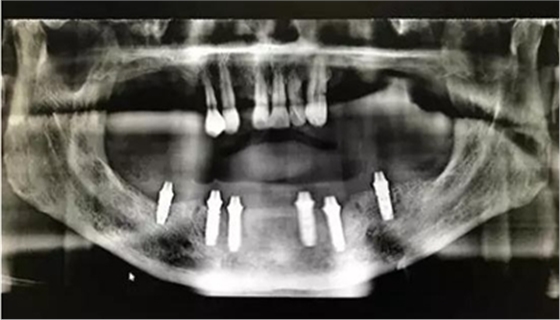

患者男,喜歡抽煙喝茶,有重度牙周病,下頜的牙齒已經(jīng)完全拔除,上頜牙齒在CT中可見(jiàn),牙槽骨吸收很?chē)?yán)重,牙根部分暴露,粘膜萎縮。要求:進(jìn)行下半口固定義齒即刻修復(fù)。

從CT可以看出患者前牙區(qū)牙槽骨非常薄,有的地方3.5mm不到,左側(cè)4號(hào)牙位有嚴(yán)重的骨吸收,需要進(jìn)行植骨,后牙區(qū)離神經(jīng)管較近,設(shè)計(jì)種植短粗型種植體。

通過(guò)術(shù)前精確的設(shè)計(jì),避開(kāi)了患者骨壁較薄需要做骨劈開(kāi)的區(qū)域,避免了大翻瓣造成較大創(chuàng)傷,大大提高了患者的舒適度。

全程手術(shù)采用小翻瓣微創(chuàng)種植,選擇初期穩(wěn)定性較好的植體進(jìn)行即刻負(fù)重。整個(gè)手術(shù)從開(kāi)始到最終戴上臨時(shí)牙,只花費(fèi)2個(gè)小時(shí)的時(shí)間,就讓患者恢復(fù)了完美笑容。數(shù)字化種植為醫(yī)生和患者帶來(lái)不一樣的感受!